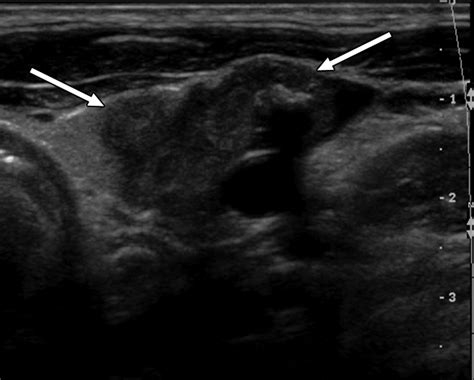

Thyroid Ultrasound Uses sound waves to create images of the thyroid, helping to determine if a nodule is solid or fluid-filled.